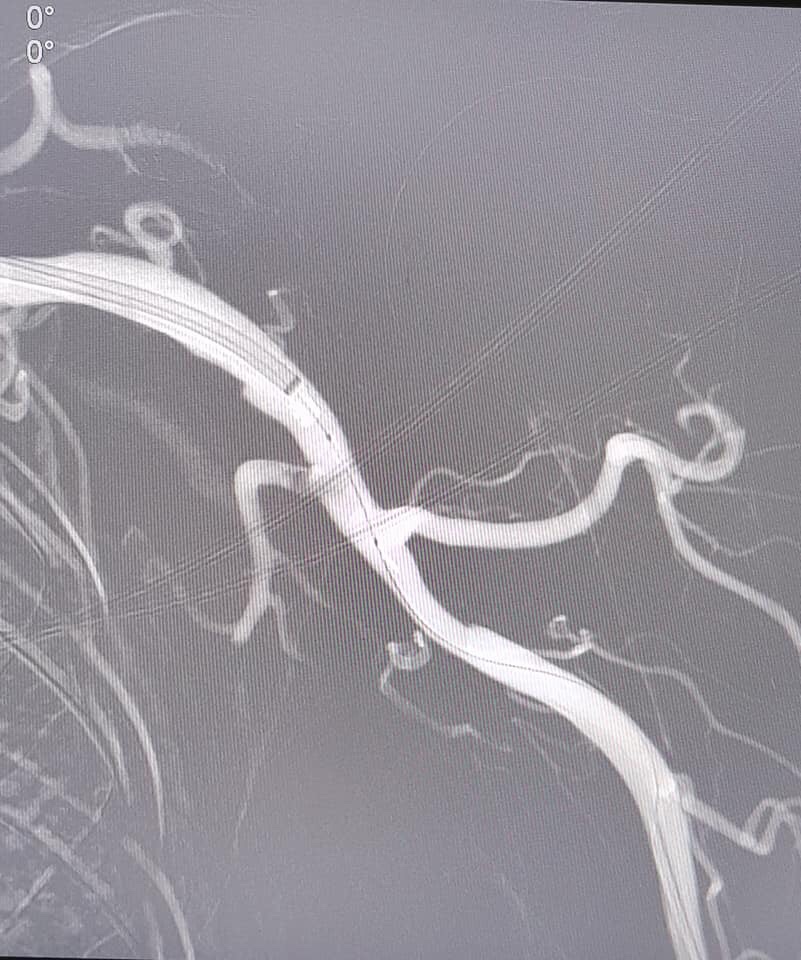

![]() Nhờ hệ thống chụp mạch số hóa xóa nền, các bác sĩ đã dùng hệ thống hút huyết khối cỡ lớn dành cho mạch ngoại biên, hút ra nhiều huyết khối, tái thông mạch máu chi trái cho bệnh nhân |

Sau 3 tiếng can thiệp, bệnh nhân được tái thông hoàn toàn động mạch từ nách tới cẳng tay. Hình ảnh chụp DSA cho thấy huyết khối đã được hút hoàn toàn, máu tươi đã được tái thông trở lại. Nhờ đó các triệu chứng lâm sàng của bệnh nhân được cải thiện ngay, bàn tay hồng trở lại, có cảm giác, cử động bàn tay đã được hồi phục.